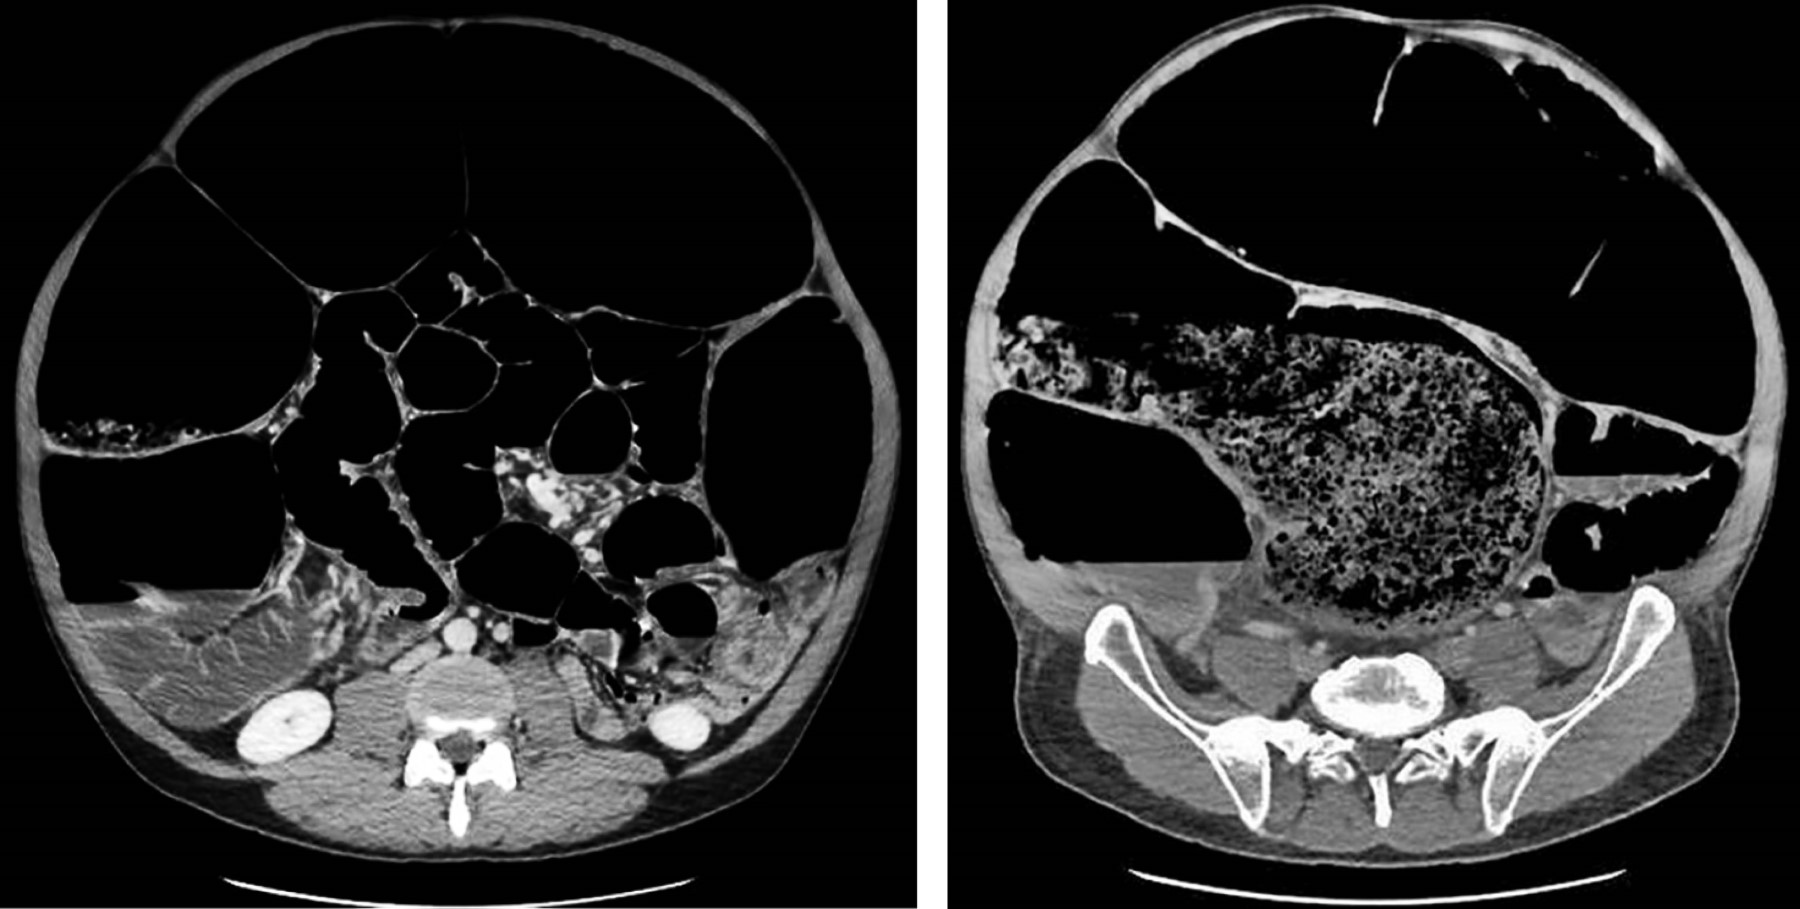

En la primera gasometría resulta llamativa la escasa afectación del equilibrio ácido-base (pH 7.4, PCO2 40.4 mmHg, CO3H- 28.3 mEq/L) e iónico (K+ 3.4, Na++ 135, Ca++ 1.10, Cl- 97), aunque presenta hemoglobina 16.4 g/dL y lactato 3.8 mmol/L. La analítica muestra 520,000 plaquetas/µL, sin afectación renal (urea 51 mg/dL, creatinina 1.16 mg/dL) ni trastornos de la coagulación (INR [International Normalized Ratio] 1.16, TTPAratio [Tiempo De Tromboplastina Parcial Activado-Relación] 1.11). La tomografía axial computarizada (TAC) muestra un gran fecaloma en ampolla rectal que provoca dilatación significativa colorrectal (16 cm en colon transverso y 13 cm en ciego) de íleon y yeyuno distal (Figuras 2 y 3). El estómago e intestino delgado proximal están colapsados y no existe neumoperitoneo ni líquido libre intraabdominal.

Figura 2

Figura 3